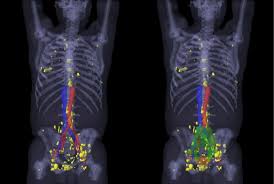

Psma Pet Ct Visualizes Prostate Cancer Recurrence Early Impacts Radiation Therapy from scx2.b-cdn.net A sign that your cancer may have returned is if your psa level has risen by 2ng/ml or more above its lowest level. If cancer is found after treatment, and after a period of time when the cancer couldn't be detected, it's called a cancer recurrence. Twenty to 30 percent of men who have been successfully treated for prostate cancer will experience a relapse more than five years after treatment, even if they have received a. If the psa starts to rise again after it has gone down to zero or close to zero, this may signal that the prostate cancer has returned. The psa test is a very effective way of checking how successful your treatment has been. Prostate cancer metastasis may be suspected if you have specific symptoms such as new lower back pain or elevated liver enzymes. A frequently asked question is 'how can the cancer come back if the prostate has been removed?' the explanation is that, as with any cancer, if cancerous cells migrate out of the organ in which they arose before the organ is removed (or treated with radiotherapy), they can settle and grow elsewhere. But the effect of a.